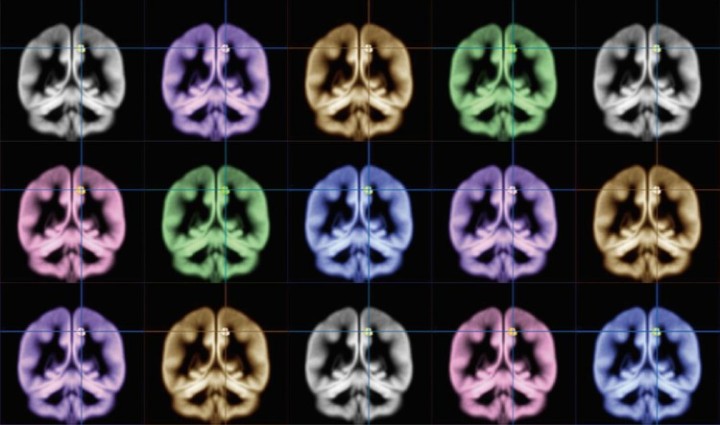

Un equipo de investigadores de la Universidad de Kioto (Japón) ha conseguido mapear el origen de la felicidad en el cerebro a través del uso de resonancias magnéticas. Su estudio ha revelado que las personas felices tienen mayor cantidad de materia gris en el precúneo, una región cerebral que se activa al experimentar lo que nos ocurre de forma consciente. El hallazgo allana el terreno hacia una forma de medición objetiva de la felicidad y también señala que ejercicios como la meditación pueden potenciar este estado.

Por eso, el científico y sus colaboradores se dispusieron a entender las claves del “cerebro feliz”. Para ello escanearon los cerebros de un grupo de voluntarios, usando resonancias magnéticas. También se hizo a los participantes en el estudio una encuesta sobre su nivel de felicidad, el grado de intensidad con que sentían sus emociones, y el nivel de satisfacción vital que tenían.

Todos estos análisis revelaron que aquellos voluntarios que reflejaban mayor felicidad en las encuestas presentaban más masa de materia gris en el precúneo. En otras palabras, las personas que sentían la felicidad de manera más intensa, la tristeza de forma menos intensa y que eran más capaces de encontrarle un significado a la vida eran aquellas que tienen una precuña mayor.